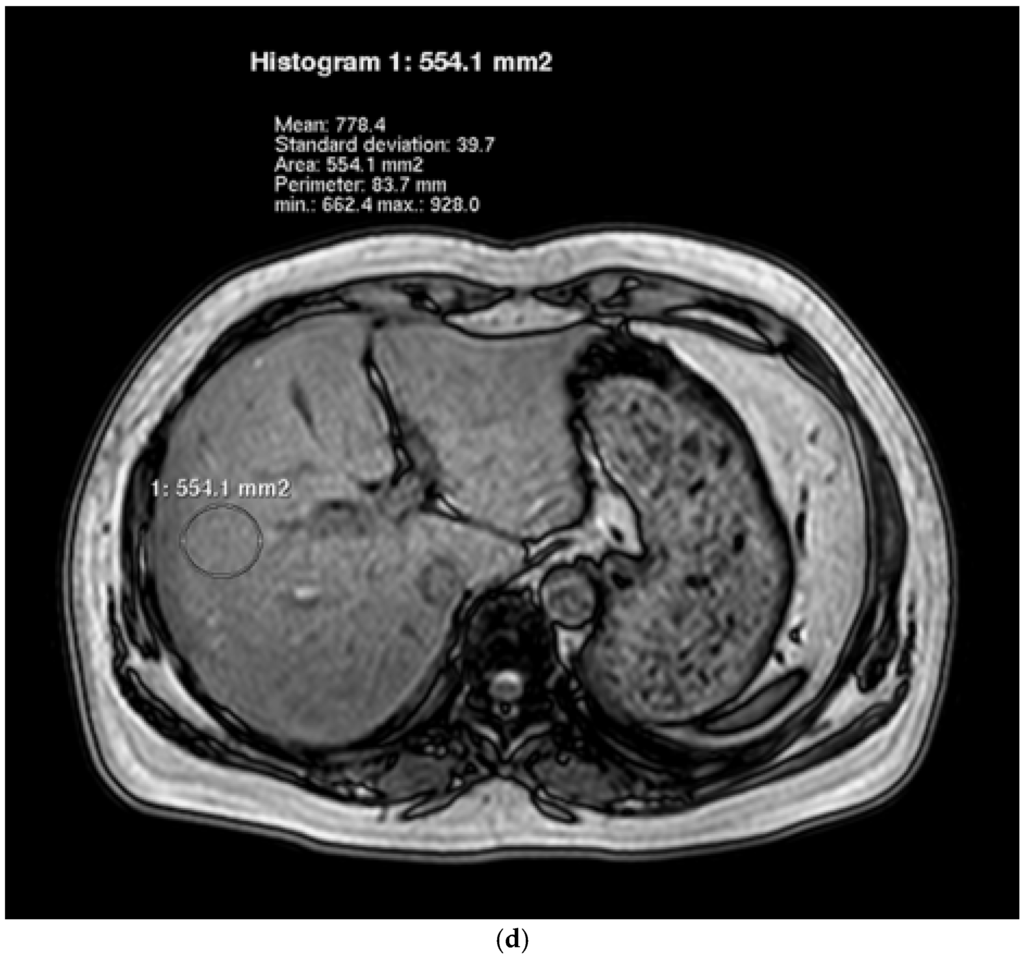

2.5. Hepatic Lipid Contents Measurements